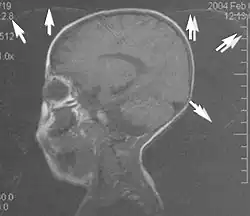

Fig. 8. Gibbs artifact (T1 sagittal study of the brain).[1]

Gibbs artifacts or Gibbs ringing artifacts, also known as truncation artifacts are caused by the under-sampling of high spatial frequencies at sharp boundaries in the image.[5][6] Lack of appropriate high-frequency components leads to an oscillation at a sharp transition known as a ringing artifact. It appears as multiple, regularly spaced parallel bands of alternating bright and dark signal that slowly fade with distance (Fig. 8). Ringing artifacts are more prominent in smaller digital matrix sizes.[1] Methods employed to correct Gibbs artifact include filtering the k-space data prior to Fourier transform, increasing the matrix size for a given field of view, the Gegenbauer reconstruction and Bayesian approach.[1]